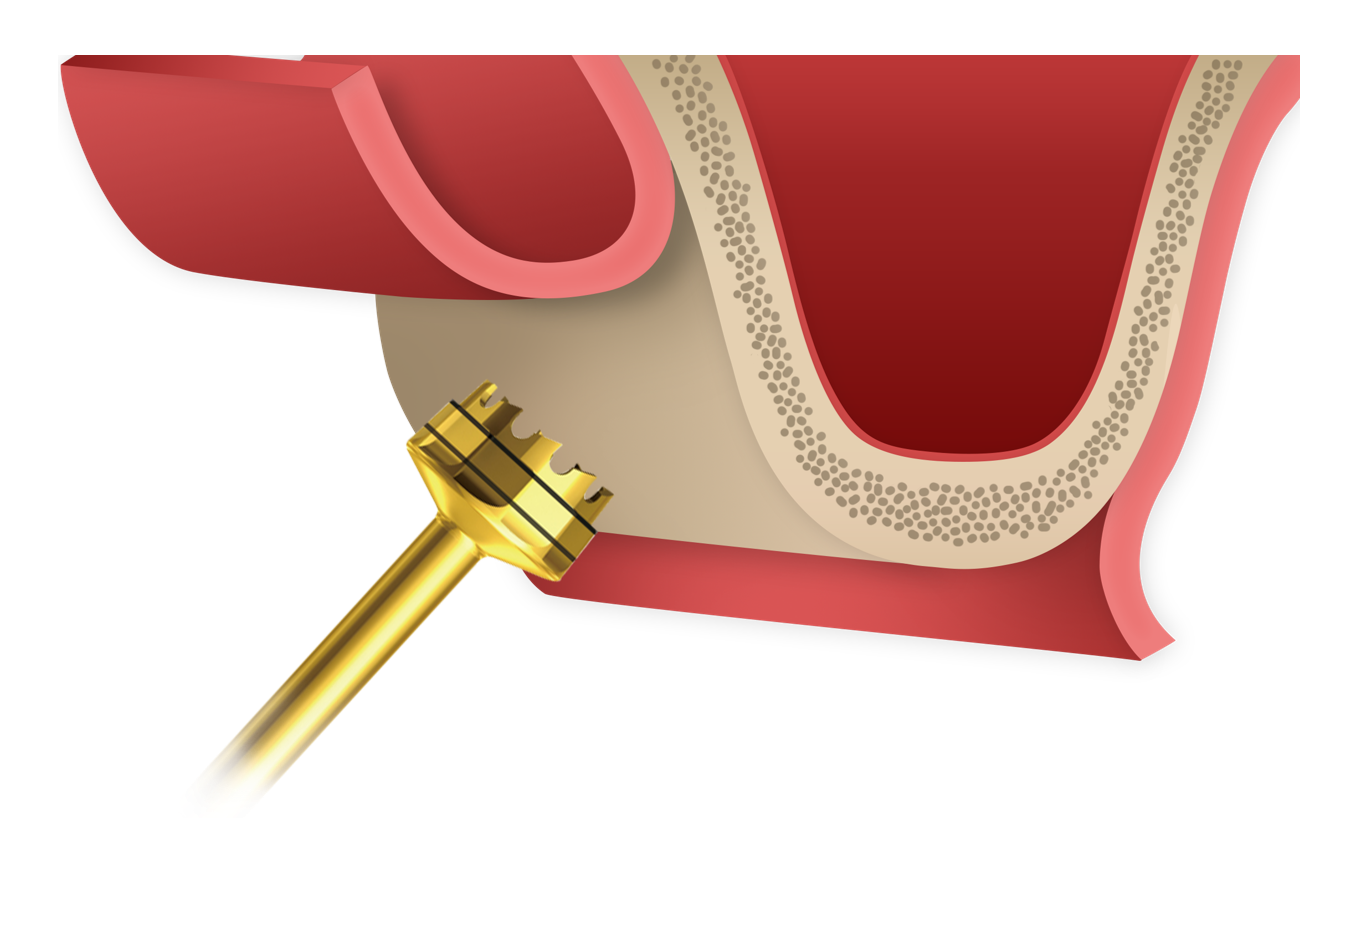

Crestal Drill

Enables controlled and predictable access to the sinus floor with minimal apical pressure.Designed to support precise drilling depth control while reducing the risk of sinus membrane perforation.